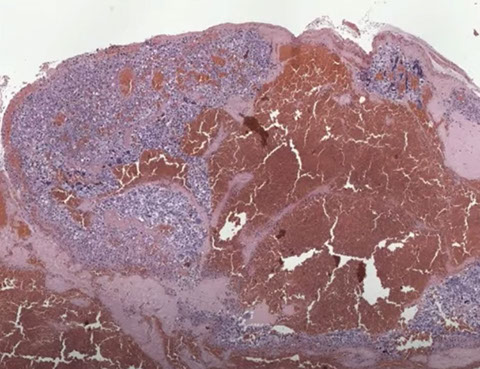

CHM

Early complete CHM

Complete Hydatidiform Mole (CHM)

Micro: Diffuse, circumferential trophoblastic prolif of uniformly enlarged, avascular edematous villi c marked prolif or trophoblasts that can be atypical

- early complete moles have uniform pop of villi that are big for gestational age, and villous edema c central cistern formation may not be present

- trophoblastic proliferation may also be focal or less developed in early dz

- villi have primitive appearance c inc mesenchymal cellularity and karyorrhexis and necrobiosis (not seen in partial mole or hydropic abortus)

CHM gross

Histologic features of a CHM

Characteristic findings in CHM with cavitation and absence of fetal vessels. Note the contents completely degenerating and filled with protein rich fluid on the left.

CHM. Trophoblast hyperplasia which is exuberant and circumferential

Early CHM. Looks like toes on a foot with deep clefting. Note the blue myxoid stroma. Pitfall: Can be found in early gestations.

CHM. Has features of early CHM (like the blue myxoid stroma with the toes on the left middle) and of more classical CHM on the right

Early CHM. Seeing earlier and earlier CHMs due to ultrasound, here note the stromal and vascular degeneration. Pitfall is that you don't want to overcall missed abortion which can have similar degeneration.